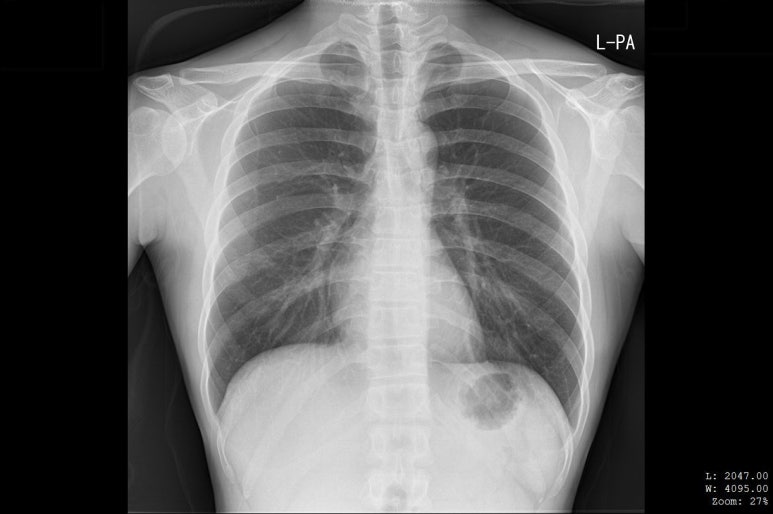

해당 환자분의 X-RAY 영상, 골절선이 보이지 않습니다.

병원에서 X-ray상

뼈는 멀쩡하다고 합니다.